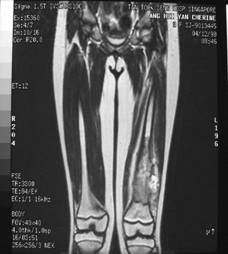

Follow Up

Leg length equalised but with different knee height

Final result with grateful patient and mother